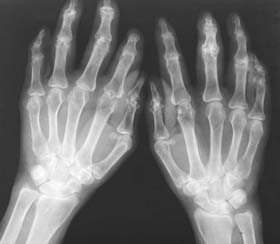

双手X线:骨质普遍疏松,掌指多个间隙变窄。

(图:患者双手X线示)